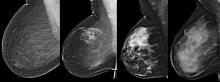

May 23, 2014 — Visage Imaging Inc. exhibited the latest release of the Visage 7 enterprise imaging platform at the 2014 Society for Imaging Informatics in Medicine (SIIM) annual meeting in Long Beach, Calif. The latest release, version 7.1.5, includes optimized navigation and tools and significant speed enhancements to Visage 7’s performance with massive digital mammography and digital breast tomosynthesis (DBT) studies.